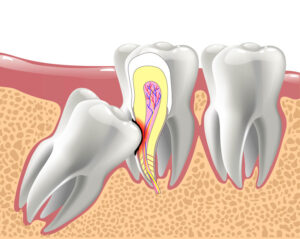

Looking for a permanent tooth replacement option? Tooth implants in Monroeville, PA, are a trusted, lasting, and reliable tooth replacement option. With tooth implants, one

Looking for a permanent tooth replacement option? Tooth implants in Monroeville, PA, are a trusted, lasting, and reliable tooth replacement option. With tooth implants, one

When people have had one or more missing teeth for a long period of time, then they may need a bone grafting procedure before they

Dental implants in Greensburg, PA are considered to be the gold standard tooth replacement option. One of the main reasons dental implants are a gold

Dental implants are a proven way to replace one or more missing teeth. No matter how skilled and practiced a dental professional is at restoring

The problem with replacing missing teeth with traditional dentures, is that they do not replace the patients missing tooth roots. When missing tooth roots are